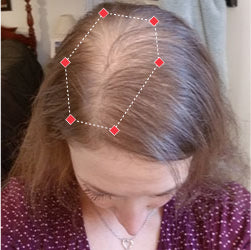

Indications for Use

The iRESTORE Hair Growth System Elite is indicated to promote hair growth in males who have Norwood-Hamilton Classifications of IIa to V and in females who have Ludwig-Savin Classifications I to II, and in both with Fitzpatrick Skin Phototypes I to IV. In other words, iRESTORE is not intended for people who are bald or have advanced hair loss.

Read more in our user manual for Indications of Use, Contraindications, Warnings, and Precautions to find out if iRESTORE is suitable for you.

Laser therapy works to reactivate thinning and dormant hairs. For completely bald areas of the scalp, there may be no way to promote hair regrowth. If you still have hair follicles, laser therapy may be beneficial to you.

Not sure? Email us to have our specialists evaluate your scalp conditions to see if iRESTORE is suitable for you.